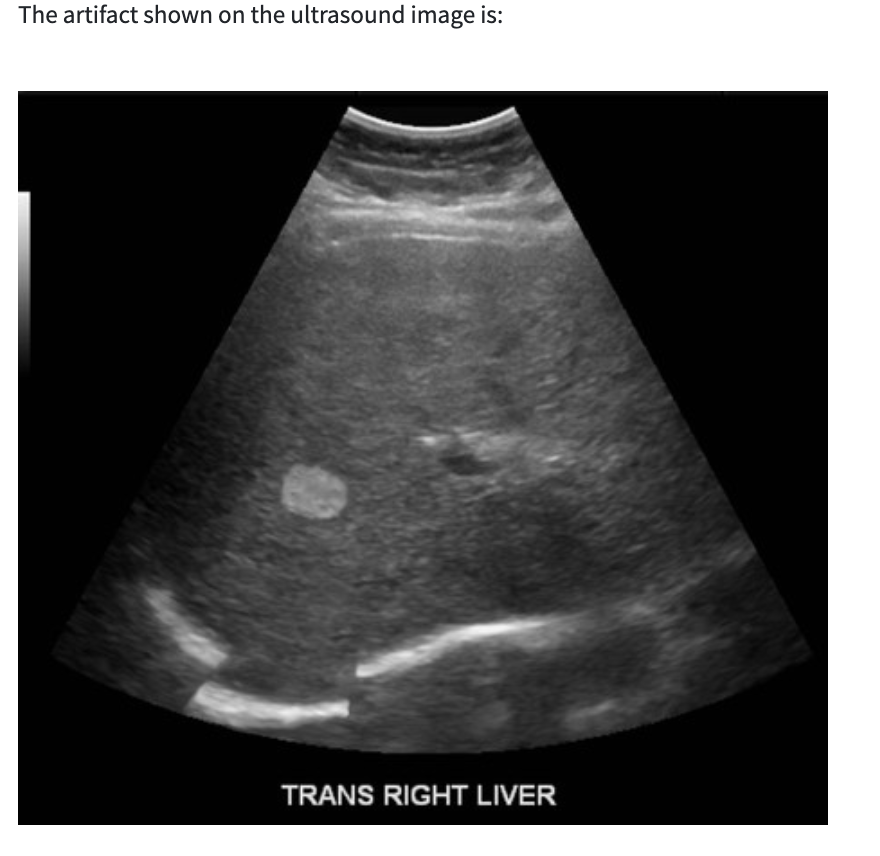

increased through transmission (acoustic enhancement)

opposite of shadowing. beam runs into material (fluid) that attenuates sound LESS than the surrounding tissue and strength of the beam distal to the structure appears BRIGHTER than the surrounding field